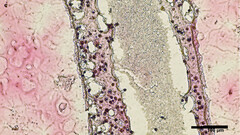

Científicos de la Universidad de la Columbia Británica (UBC) han conseguido imprimir en 3D réplicas de estructuras tubulares productoras de esperma hechas con células testiculares viables. El material de bioimpresión se obtuvo mediante la biopsia de células madre testiculares de pacientes con azoospermia no obstructiva (NOA), la forma más grave de infertilidad masculina. Esas protocélulas se cultivaron y multiplicaron antes de imprimirlas en 3D en una estructura tubular similar a las que producen esperma en los testículos humanos

El método de bioimpresión no sólo tuvo éxito en cuanto a la supervivencia de las células, sino que al cabo de 12 días se examinaron los tubos y el material "había madurado en varias de las células especializadas que intervienen en la producción de esperma"; además, los tubos testiculares de imitación "mostraban una mejora significativa en el mantenimiento de las células madre espermatogonias, ambos signos tempranos de la capacidad de producción de esperma", dice el informe. Según el investigador principal del estudio, el Dr. Ryan Flannigan, profesor adjunto de urología de la UBC:

El objetivo del equipo de investigación es ahora experimentar con la alimentación de las células bioimpresas con diversos nutrientes y factores de crecimiento adecuados para inducirlas a una producción de esperma viable que pueda utilizarse posteriormente en nuevos tratamientos de la infertilidad para las parejas que intentan concebir.